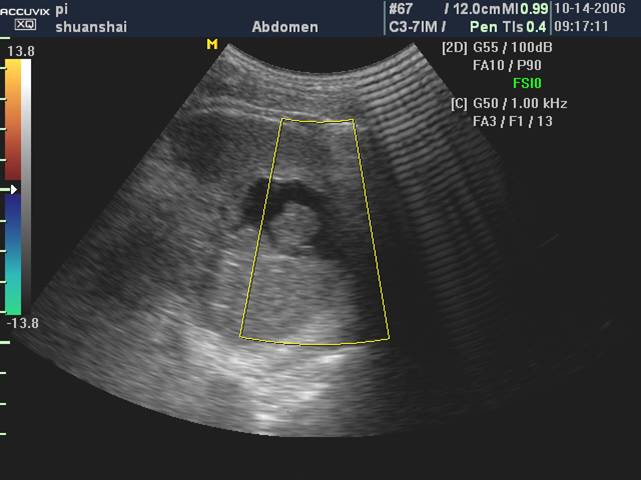

彩色多普勒

脾挫伤和血肿内无血流信号

包膜下脾破裂(脾包膜下血肿)

脾包膜下血肿常伴有包膜一表浅部位的脾实质挫裂伤。

声像表现:该处包膜隆起,呈弧形凸出,包膜下为梭形无回声或低回声区。血肿内可有低回声团块和沉淀物,也可有条索状分隔样结构。